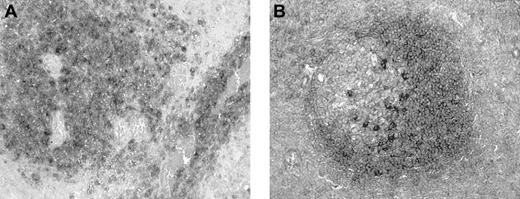

Expression of BCA-1 transcript was demonstrated in 8 of the 8 tumor samples examined by in situ hybridization (Figure5A). Although simultaneous immunophenotyping was not performed, it appeared that tumor cells were positive, whereas vascular endothelial cells were negative (Figure 5B). However, the pattern of expression varied across the section, and some tumor cells did not express BCA-1 mRNA. No hybridization was detected in sections incubated with the BCA-1 sense mRNA probe (Figure 5C). The BCA-1 mRNA was also detected in the lymphoid follicles of human tonsil (Figure 5D), whereas no hybridization was observed when the sense probe was applied.

BCA-1 mRNA expression in PCNSL.

In situ hybridization confirms BCA-1 expression in brain biopsy specimen from a patient with PCNSL. Antisense (A) and sense (C) hybridizations are shown (hematoxylin counterstain, original magnification × 40). (B) Vascular endothelium does not appear to synthesize BCA-1 because BCA-1 mRNA is localized solely to B lymphocytes (hematoxylin counterstain, original magnification × 200). (D) In human tonsil, BCA-1 mRNA is present in the lymphoid follicles (hematoxylin counterstain, original magnification × 200).